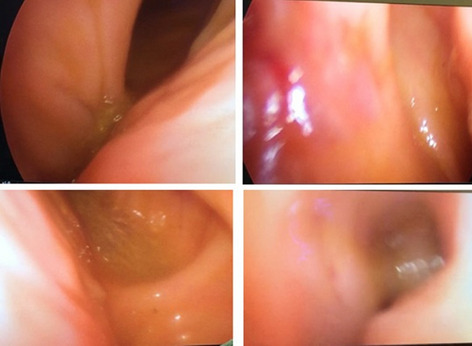

Background: Per-oral endoscopic myotomy (POEM) is an effective treatment for achalasia. Efficacy is equivalent to Laparoscopic Heller’s myotomy with the advantage of minimal access and shorter length of stay. Post-operative reflux rates are higher in POEM. The Functional Luminal Imaging Probe (FLIP) allows intraoperative measurement of lower oesophageal distensibility during per-oral endoscopic myotomy. In theory, this enables the operator to tailor the myotomy to ensure adequate distensibility whilst minimising post-operative reflux risk.

Methods: Two prospectively collected POEM databases were analysed from 2 UK tertiary upper GI centres.

The operators in each centre used intraoperative FLIP measurements to ensure adequate myotomy. Outcome measures included Eckardt score (where ≤ 3 indicated clinical success) and proton pump inhibitor use (PPI), collected at the first post-operative appointment. Length of stay was recorded, as were complications.

Results: 142 patients underwent POEM between 2015 and 2019 with 90% (128/142) clinical success. This improved to 93% (68/73) in the latter half of each series. 79% of the poor responders had previous interventions compared to 55% of responders (p = 0.09). Average post myotomy distensibility was 5.2 mm2/mmHg in responders and 3.11 in non-responders (p = 0.11). DI of > 4.5mm2/mmHg was associated with 100% clinical success. Myotomy length of < 7 cm was associated with 93% clinical success and 40% post op PPI use compared to 60% PPI use with longer myotomies. There were 2 type IIIa, 2 type IIIb and one type IV Clavien-Dindo complications.

Conclusion: This study represents one of the largest UK series of FLIP tailored per-oral endoscopic myotomy. FLIP allows intraoperative monitoring of oesophageal distensibility allowing tailoring of myotomies. Tailored myotomies ≤ 6 cm were effective and were associated with less PPI use post operatively. Early referral of patients to high volume centres, where myotomies can be tailored using FLIP may lead to improved outcomes. More collaborative data from high volume centres is needed to decipher optimal myotomy profiles.